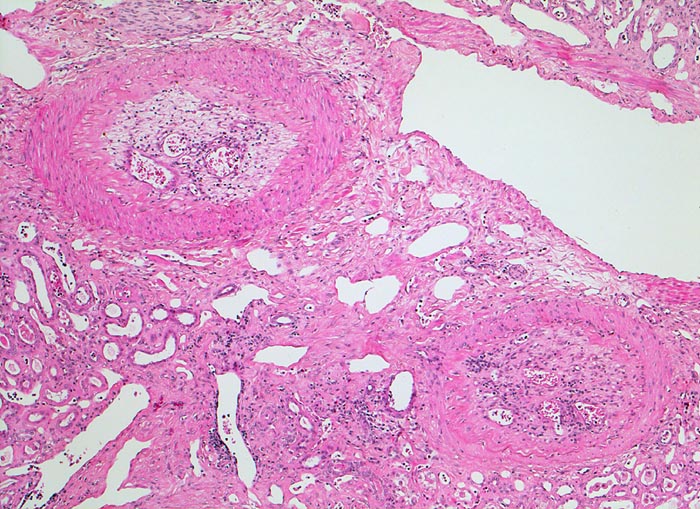

Diese intrarenalen Arterienäste weisen alte organisierte und durch kapilläre Gefässe rekanalisierte embolische Verschlüsse auf.

Chronisches Vorhofflimmern mit Morbus embolicus: anämische Infarkte verschiedenen Alters in beiden Nieren und in der Milz. Alte abgebaute Enzephalomalazie im Versorgungsbereich der Arteria cerebri media rechts.

Die meisten Arterienverschlüsse in der Niere sind embolisch bedingt. Die Niere ist wegen ihrer starken Durchblutung oft von Embolien betroffen. Da die Niere durch Endarterien versorgt wird, handelt es sich um anämische Infarkte. Thrombotische Verschlüsse bei fortgeschrittener Atherosklerose (Diabetes mellitus) oder im Rahmen einer Vaskulitis sind selten.